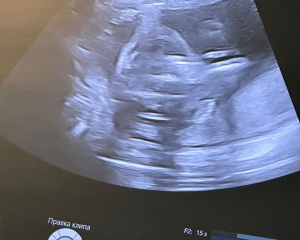

Fetal malformation was revealed in a woman in the 17th week of gestation. The prenatal board of doctors made the decision on the intrauterine drainage of fetal bladder. This intervention was necessary to prevent the pulmonary hypoplasia and preserve the normal kidney function of the unborn baby.

This operation was successful. The condition of patient is stable; the fetal development is monitored and controlled in dynamics.